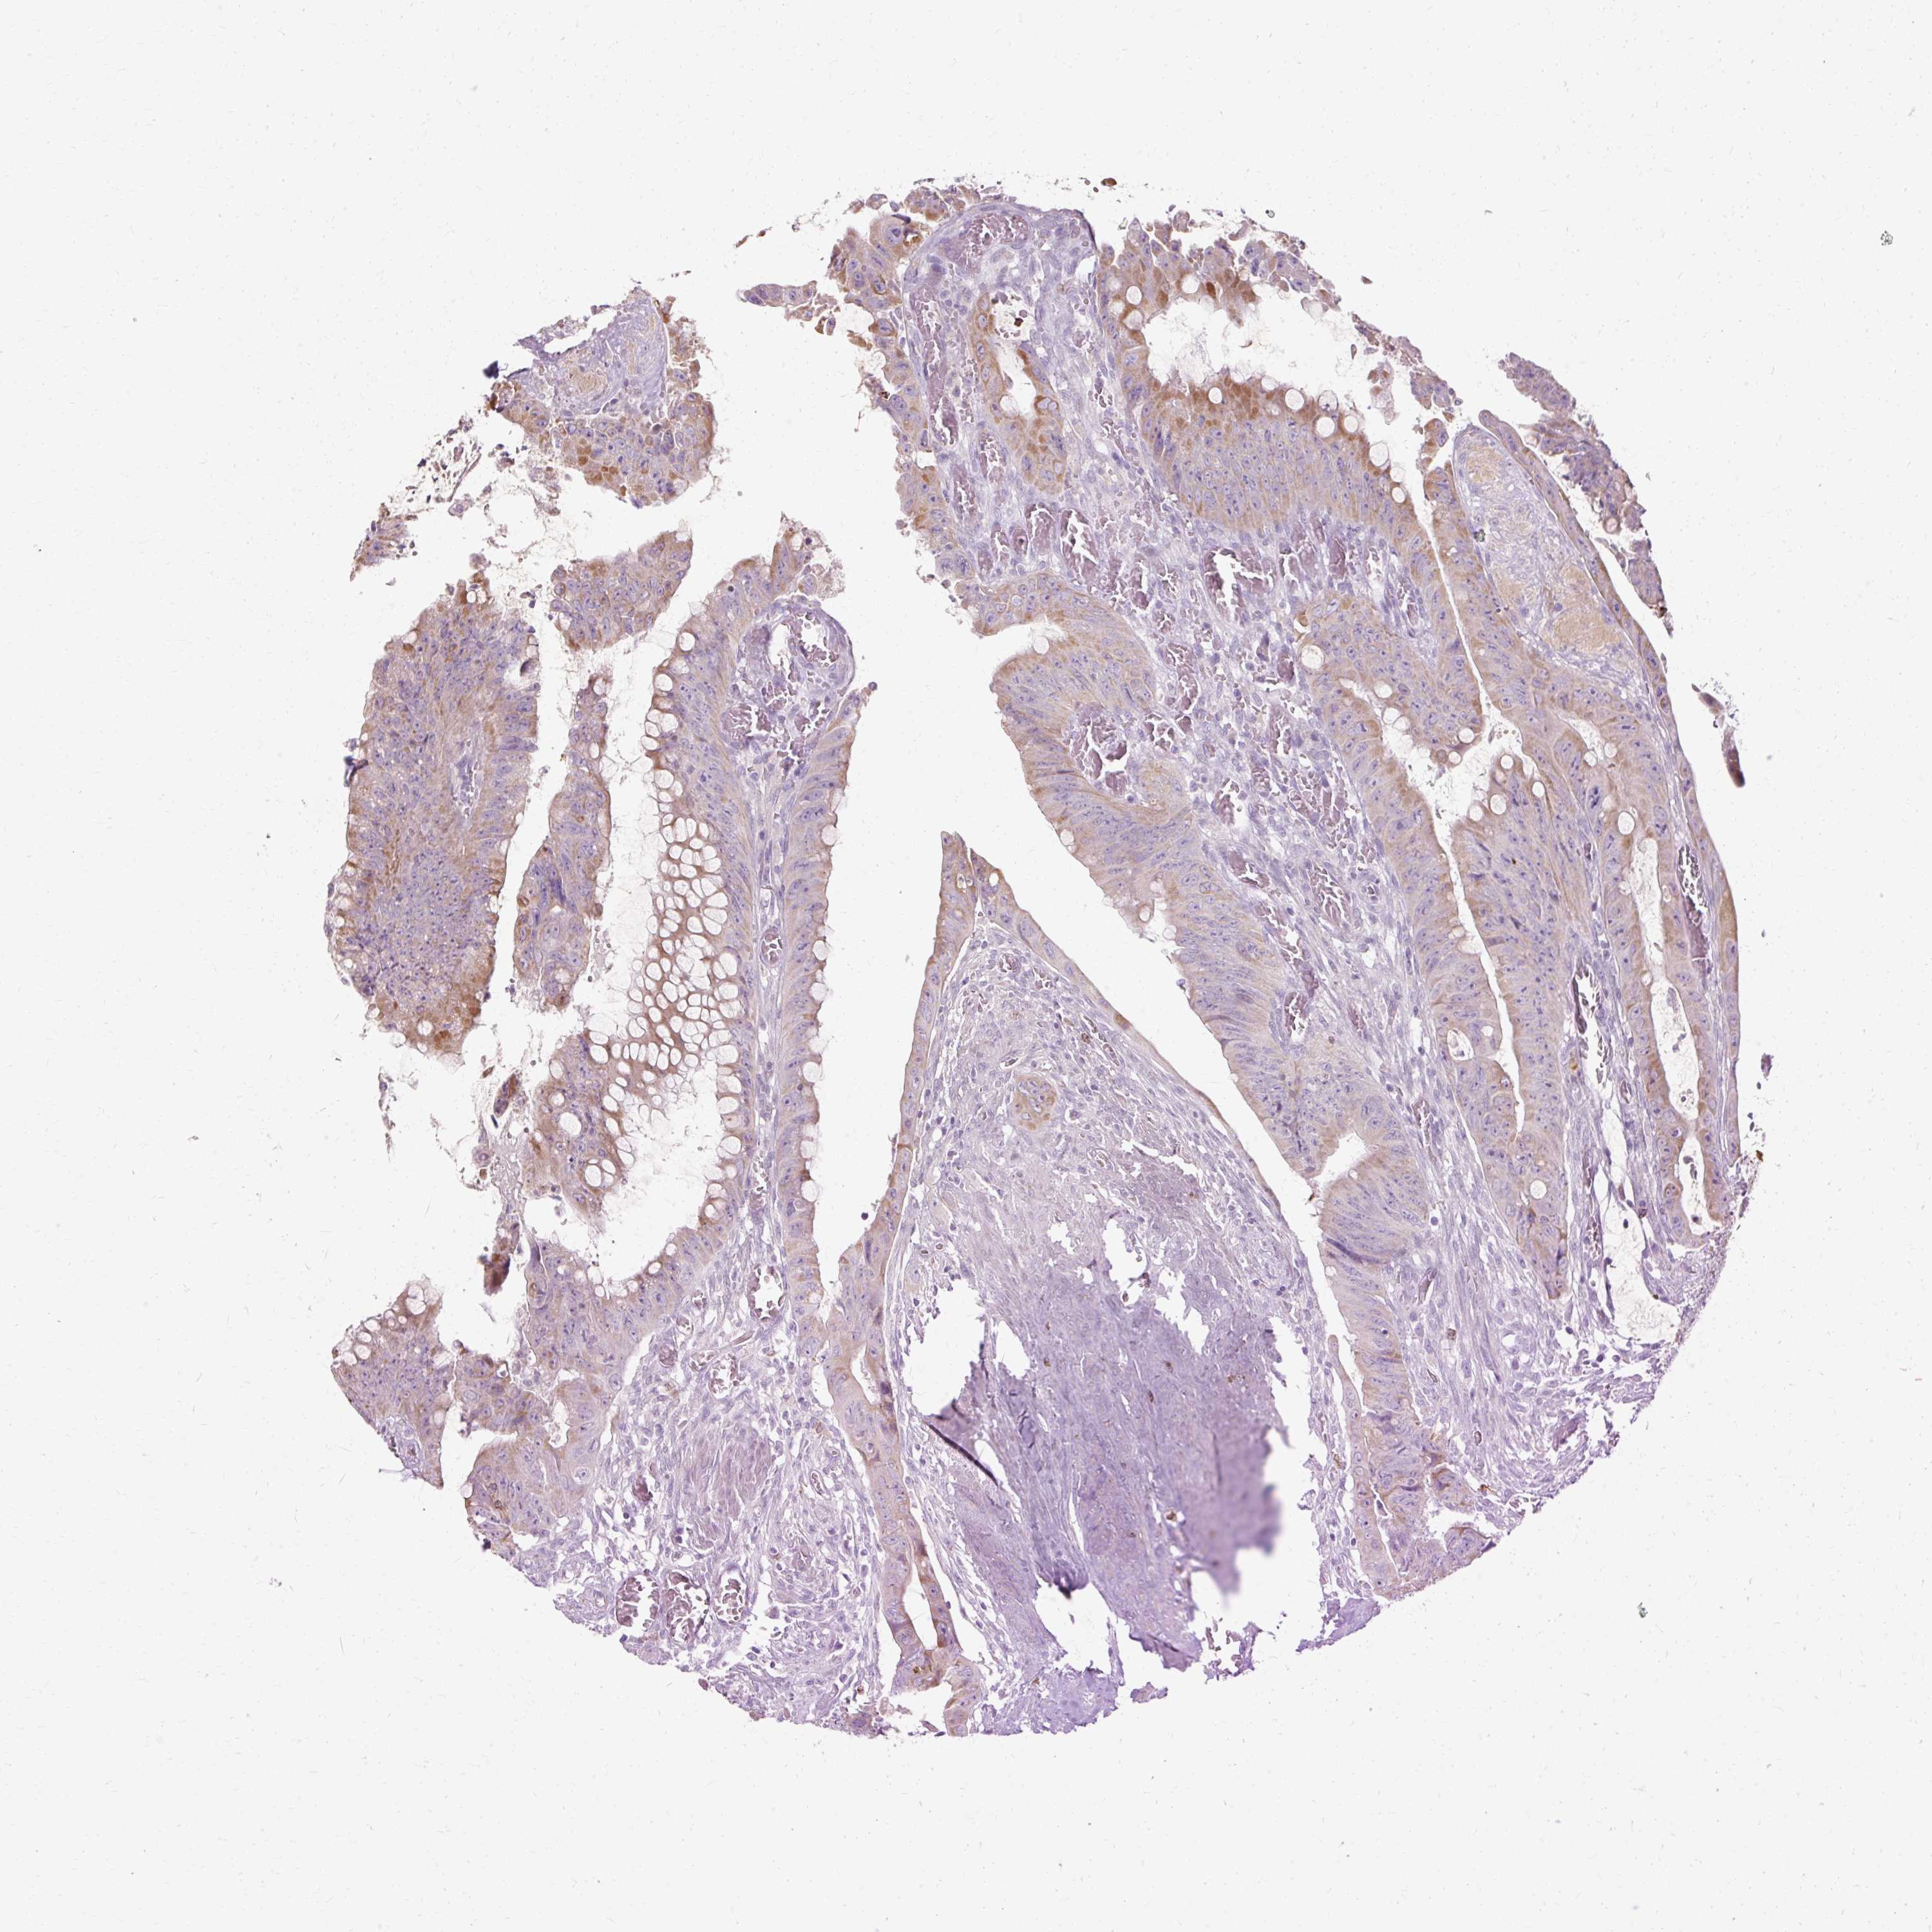

Colorectal cancer

Colon adenocarcinoma

HSD11B1 is not prognostic in Colon Adenocarcinoma (TCGA)

HSD11B1 is not prognostic in Colon Adenocarcinoma (validation)